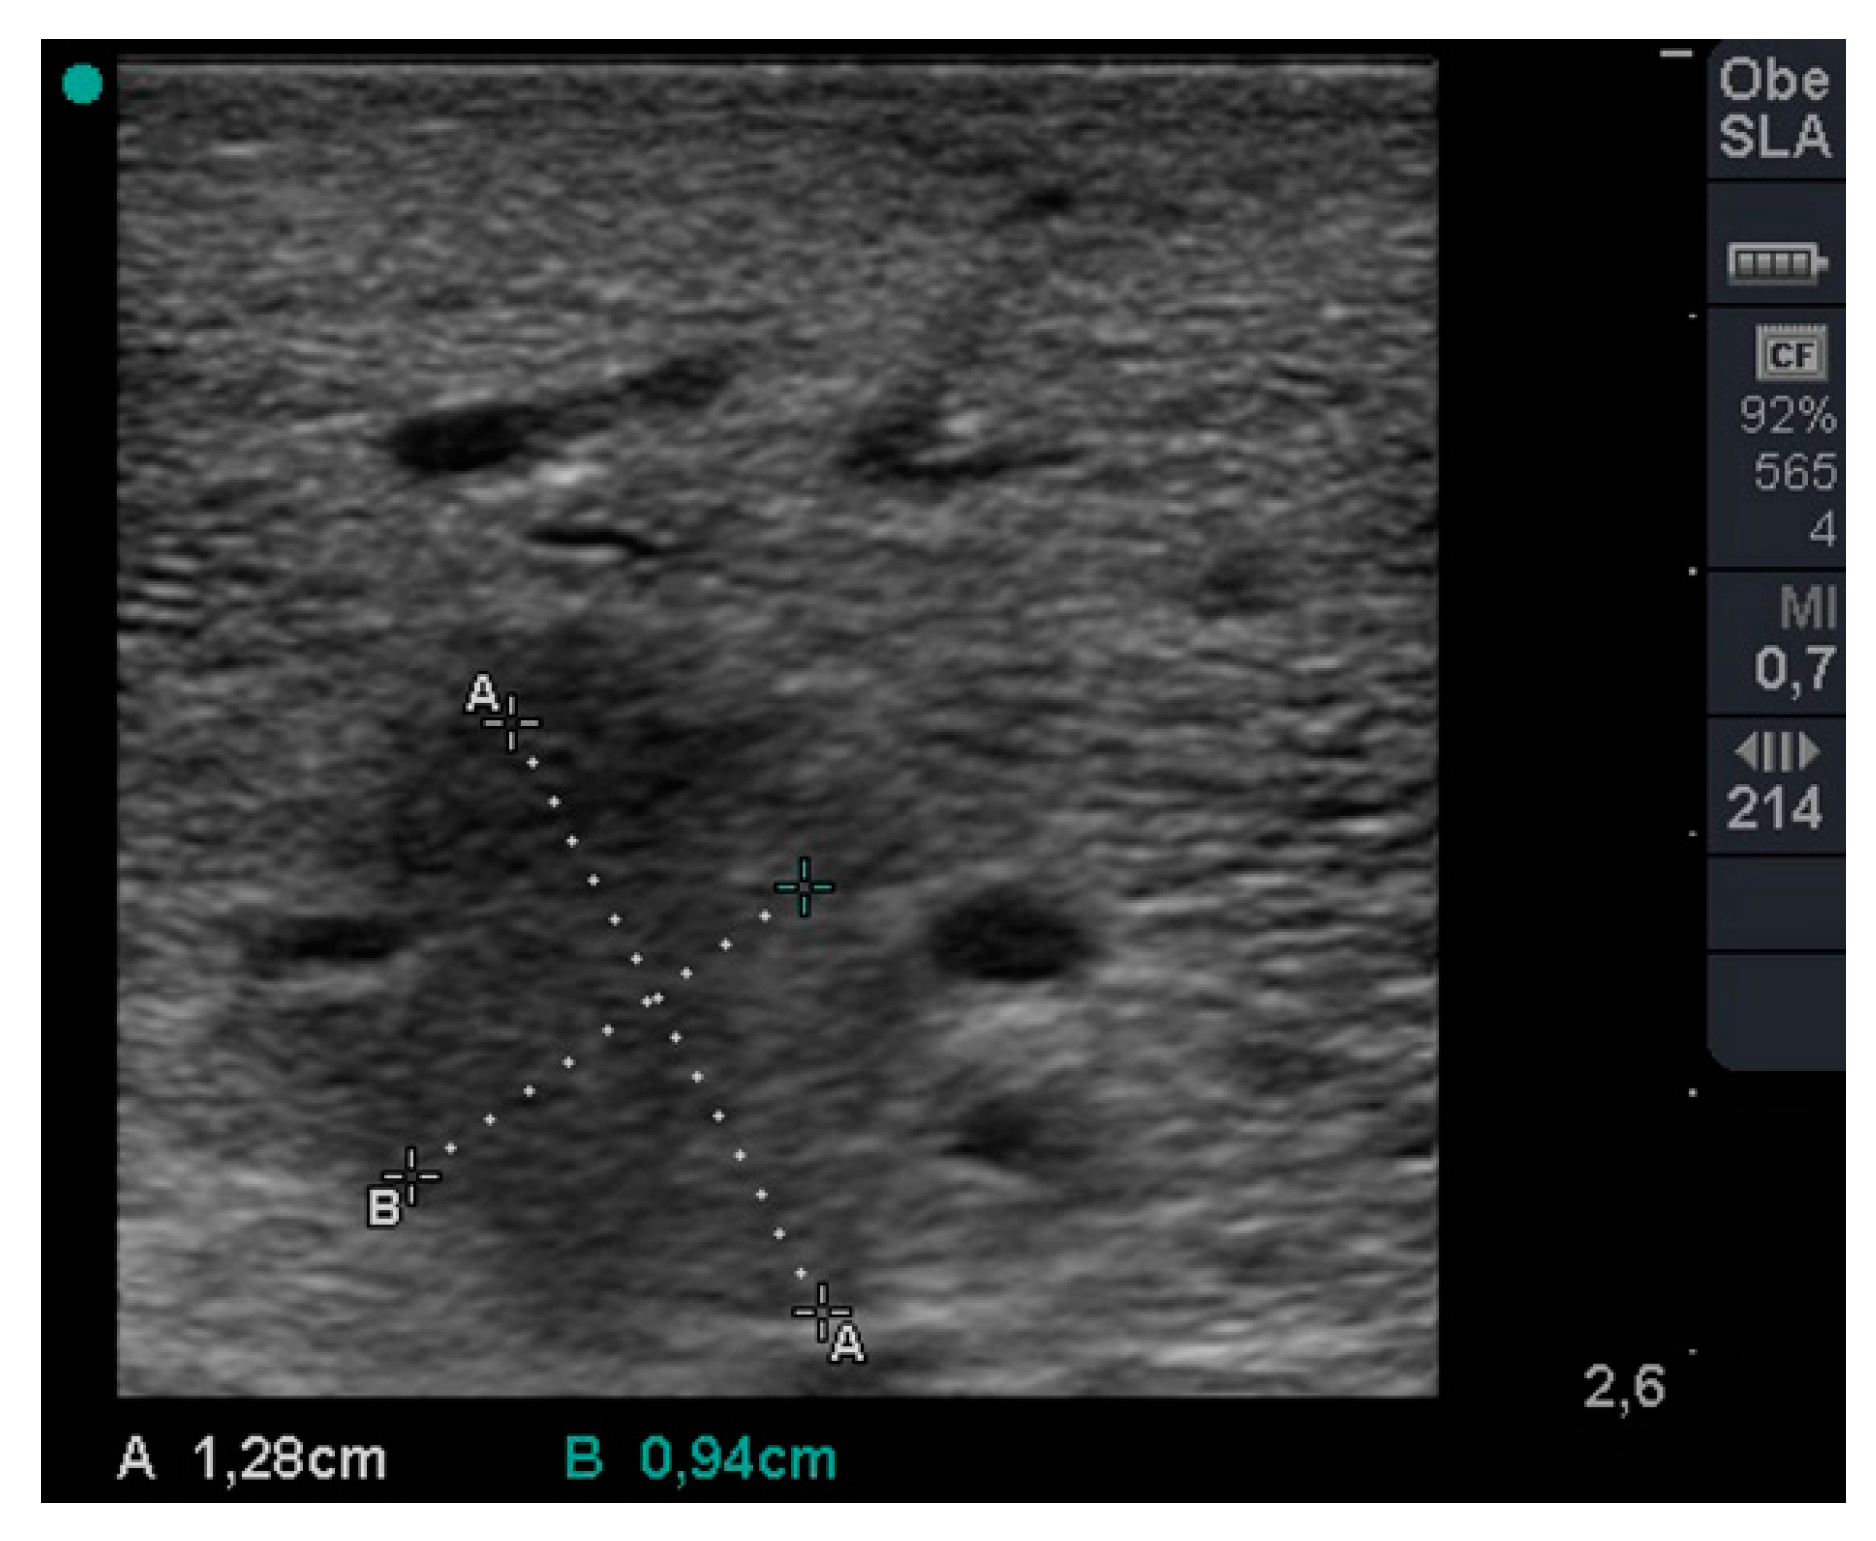

During stable flooding in-vivo with saline, unimpaired imaging without remaining air was achieved. The lung parenchyma appears homogeneous with enhanced echogenicity, where vessels and bronchi are well demarked as hypoechoic structures [18]. Trans-pulmonary imaging visualized adjacent organs such as the liver or heart (Figure 4). Doppler imaging in flooded lung is feasible and useful to detect vessels (Figure 5). No limitations regarding penetration depth were documented. High frequency linear probes (10–15 MHz) were recommended for high resolution imaging such as for small bronchi or vessels [22] (Figure 6). Using ex-vivo models and simulated intra-pulmonary nodules in-vivo, a reliable nodule detection of primary lung cancer as well as metastases were found. The tumor mass appears hypoechoic, surrounded by hyperechoic flooded lung, resulting in a high detection rate of about 100% of malignant pulmonary nodules (Figure 7), as well as simulated nodules [31]. Interestingly, the visualization is aggravated only for the bronchoalveolar cell carcinoma. The specific growth along the alveolar surface caused an echo-enhanced appearance with similar characteristics to flooded lung parenchyma [18].

Figure 5. Doppler imaging of central through flooded lung. Pulmonary artery show typical flow characteristics and adjacent bronchus with absence of Doppler signal.